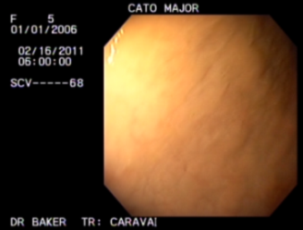

Location: Wonderful Wyoming | This is a from some of the professionals at Total Health, I just received this in an email to better explain GastroPLUS.

What makes T.H.E. unique is that we think outside of the box with all of our products. GastroPLUS specifically works completely differently than other ulcer products. Most ulcer products reduce the acid in the stomach. Even though that is what causes ulcers it is not the main issue at hand. Sometimes when you reduce the acid your horse can get protein entropy or when you take them off the horse over produces the acid and the ulcers come back worse therefore creating a vicious cycle. Our product increases the mucus lining in the horses stomach therefore helping the horse to contain and control the acid. Also our product is a complete supplement therefore it is not just for ulcers. It is also for digestive functioning and has the amino acids, vitamins and minerals your horse would need to stay healthy. My increasing mucus throughout the whole gestational track it enables us to be able to reach the hind gut. GastroPLUS is also go for horses with gestational issues such as diarrhea or a soft stool. It is safe to use long term. Most of the racehorses on our products get GastroPLUS daily at the racetrack.

I also have several scope pictures to show before and afters. pm me emails and I will forward away, just don't be eating a sammich while you look at them  |

Location: Wonderful Wyoming | Here are the graphic pics, I think I can get them on here.

(unnamed.jpg) (unnamed.jpg)

(unnamed (1).jpg) (unnamed (1).jpg)

(unnamed (2).jpg) (unnamed (2).jpg)

(unnamed (3).jpg) (unnamed (3).jpg)

Attachments

----------------

unnamed.jpg (15KB - 475 downloads) unnamed.jpg (15KB - 475 downloads)

unnamed (1).jpg (14KB - 450 downloads) unnamed (1).jpg (14KB - 450 downloads)

unnamed (2).jpg (19KB - 430 downloads) unnamed (2).jpg (19KB - 430 downloads)

unnamed (3).jpg (16KB - 478 downloads) unnamed (3).jpg (16KB - 478 downloads)

|